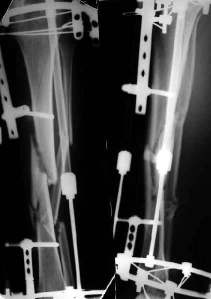

При невозможности или чрезмерной травматичности одномоментного восстановления длины можно пойти двухэтапно (аппарат, потом гвоздь). Похожий пример см. тут. Прошло уже года полтора после остеосинтеза. Может, коллега Зырянов покажет годичный результат, если есть?

Александр Николаевич, к сожалению больной не является на контрольные осмотры. Я последний раз видел больного, когда прошло 7 месяцев после операции БОС. У него все хорошо. Каких либо жалоб и ограничений в нагрузке нет. Высылаю снимки до операции и последние снимки.